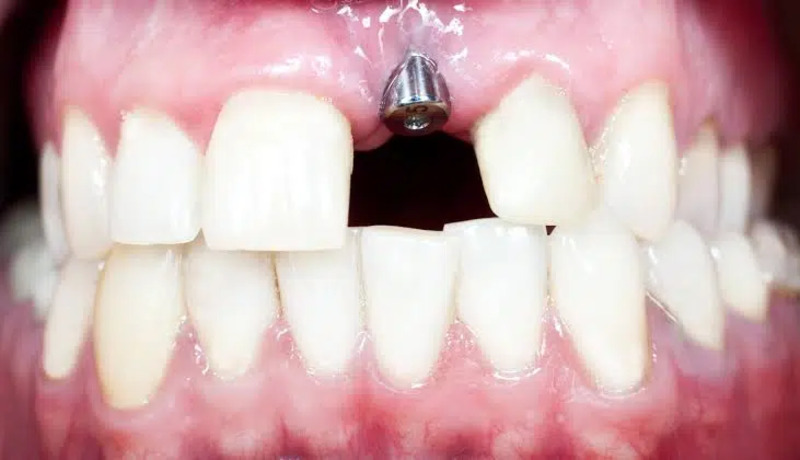

Trong trường hợp răng Implant ở vị trí răng phía trước

Khi răng Implant được trồng ở vị trí răng phía trước và cản trở sự dịch chuyển của các răng thật trong quá trình niềng, bác sĩ có thể quyết định tháo bỏ mão răng sứ trên Implant và thay thế bằng mão răng nhựa tạm thời để giúp mắc cài bám dính tốt hơn. Việc thay mão răng giúp tạo không gian linh hoạt hơn, không gây cản trở việc di chuyển của các răng thật xung quanh, từ đó bác sĩ có thể dễ dàng điều chỉnh hướng dịch chuyển của các răng thật.

Sau khi quá trình niềng răng hoàn tất và mắc cài được tháo bỏ, bác sĩ sẽ tiến hành đặt lại mão răng sứ cho Implant nhằm đảm bảo thẩm mỹ và khớp cắn chuẩn xác. Qua đó, răng sẽ được khôi phục vẻ ngoài tự nhiên và đảm bảo chức năng ăn nhai bình thường sau khi hoàn tất quá trình niềng răng.

Hình ảnh trụ Implant được đặt ở vị trí răng phía trước (Nguồn: MOD Squad Dental)